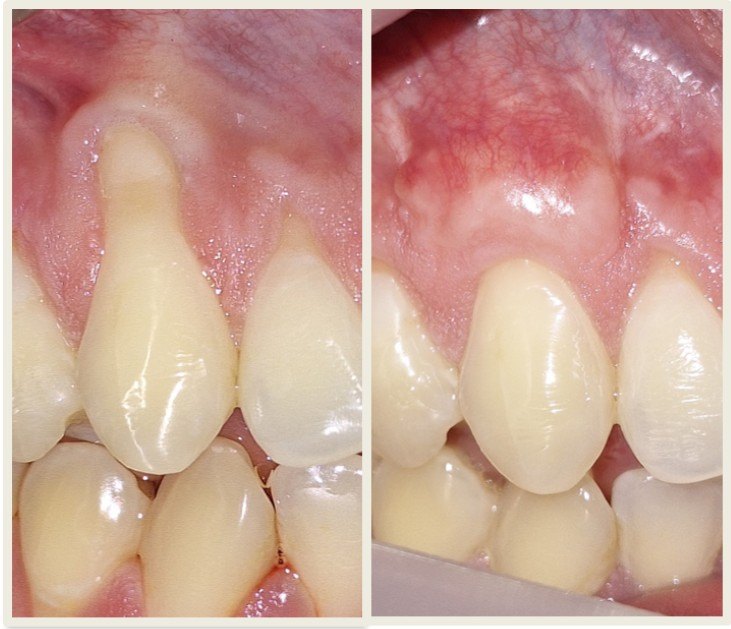

La retracción gingival, también conocida como recesión gingival, es el desplazamiento progresivo de la encía que deja expuesta la raíz del diente. Este proceso hace que tus dientes se vean más largos de lo normal y puede causar sensibilidad al frío, calor o dulces, afectar significativamente la estética de tu sonrisa y aumentar el riesgo de caries radiculares en la zona expuesta.

Una vez controladas las causas, y con un diagnóstico correcto que evalúe factores como la severidad de la recesión, el biotipo gingival, la cantidad de encía queratinizada disponible y la presencia de hueso subyacente, podemos reconstruir la encía perdida y mejorar su arquitectura a través de cirugía plástica periodontal. Utilizamos técnicas de microcirugía avanzadas que ofrecen resultados favorables y predecibles, permitiendo en muchos casos la recuperación total del tejido perdido con mínimas molestias post-operatorias.

No todas, pero muchas sí. El pronóstico de cobertura radicular depende de varios factores: la clasificación de la recesión (si hay pérdida de hueso interdental o no), el biotipo gingival, la presencia de encía queratinizada, y hábitos como el tabaquismo. En recesiones de Clase I y II de Miller (sin pérdida de hueso interdental), podemos lograr cobertura completa en más del 90% de los casos. En recesiones más complejas, podemos lograr cobertura parcial significativa y mejorar sustancialmente la estética y protección del diente. Durante tu evaluación, te daremos un pronóstico realista específico para tu caso.

Los resultados son progresivos. Verás una mejoría inmediata después de retirar los puntos (aproximadamente a los 10-14 días), pero el tejido necesita tiempo para madurar y estabilizarse. A los 3 meses, tendrás una muy buena idea del resultado final, pero la maduración completa del tejido y la estabilización del color y textura ocurren entre los 6-12 meses post-cirugía. Durante este período, tendrás controles periódicos donde monitoreamos la evolución y te damos indicaciones específicas para cuidar la zona tratada y optimizar el resultado final.